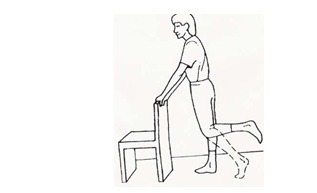

بایستید و پای عمل شده را اندکی خم کنید و همزمان با به داخل کشیدن باسن، زانو را صاف کنید. 5 ثانیه در این حالت بمانید. این حرکت را 10 بار تکرار کنید.

بایستید و پای عمل شده را اندکی خم کنید و همزمان با به داخل کشیدن باسن، زانو را صاف کنید. 5 ثانیه در این حالت بمانید. این حرکت را 10 بار تکرار کنید.

سطح ثابت و پایداری را بگیرید و خود را روی پنجهها بالا بکشید و پاشنهها را بلند کنید. این حرکت را 10 بار تکرار کنید.